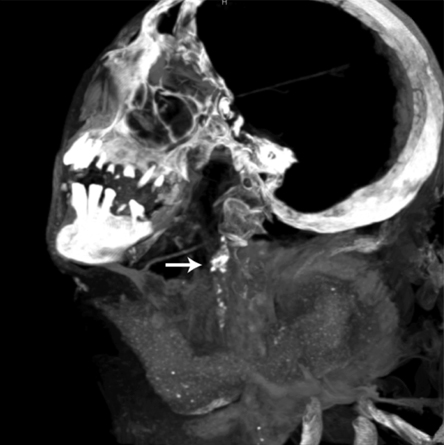

UNWRAPPED Studies of mummies from around the world (an ancient Egyptian mummy undergoing a CT scan shown) reveal that hardening of the arteries has been a problem for more than 5,000 years.

4C/PFO from R.C. Thompson et al/Global Heart 2014

In the June Global Heart, researchers present evidence of heart disease from a diverse array of mummies including the famous 5,300-year-old Tyrolean Iceman, 76 ancient Egyptians, 51 native Peruvians dating from the 3rd to 16th centuries, five Pueblo Indians who lived in Utah about 1,000 years ago, a Renaissance king, a 15th century nomad from the Gobi Desert and five 19th century hunter-gatherers from the Aleutian Islands. CT scans or autopsies revealed calcium deposits in artery walls of many of the mummies, a sign of vessel hardening.